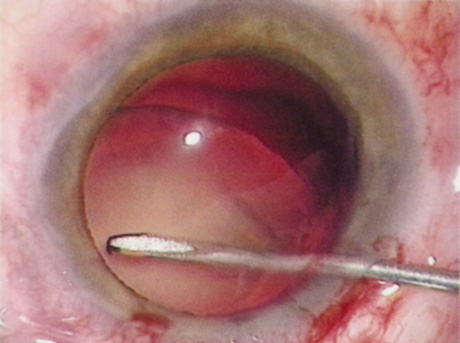

Retrobulbar Block

Retrobulbar blocks were among the earliest of orbital block techniques and have stood the test of time. Although there are many approaches to block administration, each technique intends delivery of the anesthetic medication into the intraconal space. These blocks are highly effective (about 95%) in achieving adequate ocular akinesia and anesthesia. Potential complications include retrobulbar hemorrhage,67 globe penetration,68,69 optic nerve sheath hemorrhage, extraocular muscle toxicity with persistent diplopia, and, rarely, brainstem anesthesia. Visualization of the globe is improved when using a transconjunctival approach (Fig. 6) or when the skin is indented with a cotton-tipped applicator (Fig. 7), making globe perforation less likely.

Fig. 6. Retrobulbar block using a transconjunctival approach.